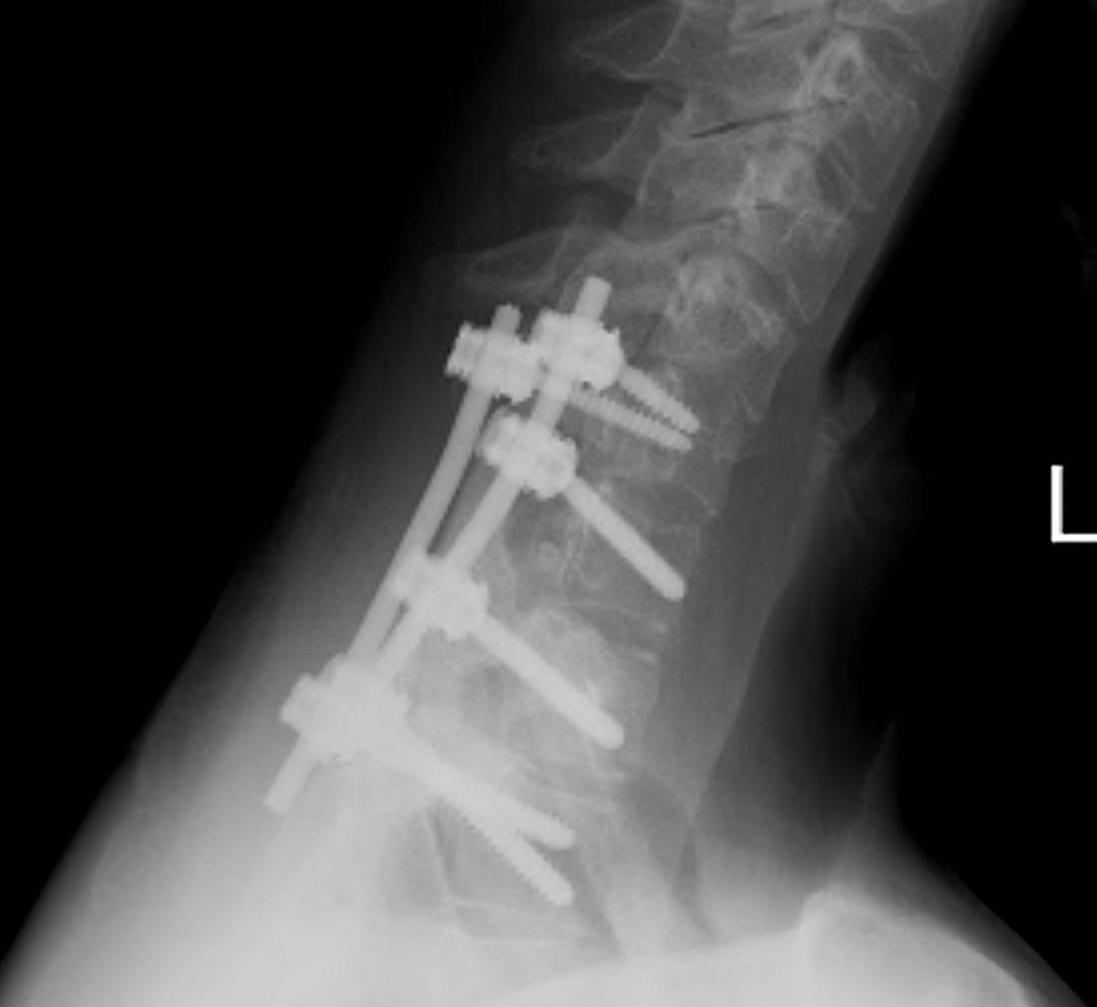

Osteoblastoma Exision and Fusion0001Osteoblastoma Exision and Fusion0002

Wide excision +/- posterior fusion

Can recur

- life long follow up